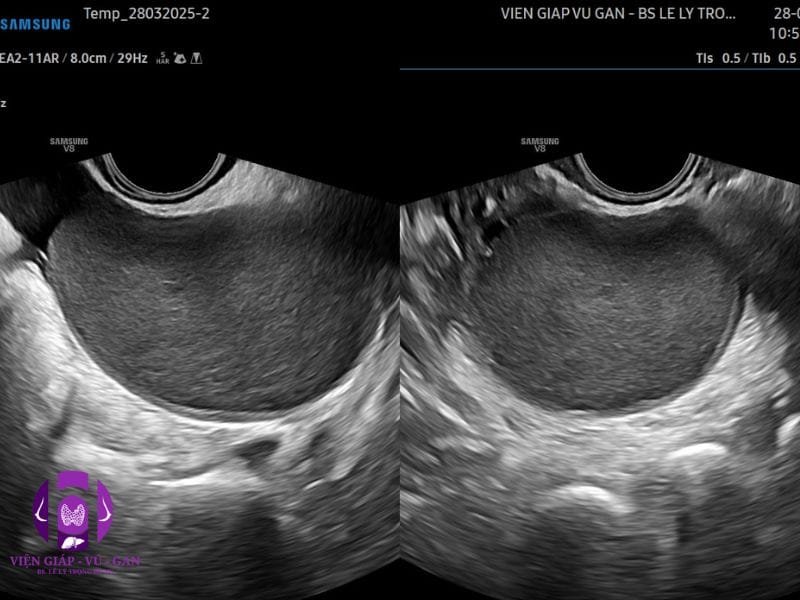

SIÊU ÂM (Máy Samsung V8)

- Tử cung: không to, đồng nhất, dAP# 40mm, nội mạc dày 8mm.

- Buồng trứng phải: không bướu

- Buồng trứng trái: có cấu trúc dạng nang đơn thùy, echo kém dạng kính mờ, bờ đều, không tăng tín hiệu mạch, kích thước từ 60×50 mm.

KẾT LUẬN: U LẠC NỘI MẠC BUỒNG TRỨNG TRÁI

- Đặc điểm hình ảnh siêu âm của u lạc nội mạc tử cung có biểu hiện khá đa dạng:

- U lạc nội mạc điển hình (50% các trường hợp )

- U nang đơn thùy

- không mạch máu

- Hồi âm kém đồng nhất (dạng “kính mờ” ) do các mảnh vụn xuất huyết.